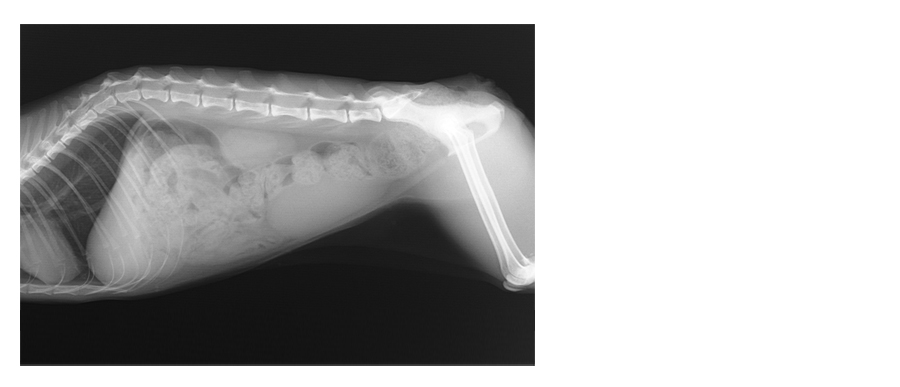

◆日本猫 6歳7か月 避妊メス 2.30㎏

◆稟告 子猫の時に保護して以来、自力排便が出来ず下剤投与、およびオーナーによる毎日の摘便処置。

肛門欠損による排泄孔の狭窄

重度の便秘

発症の原因については、先天性か後天性かは不明。